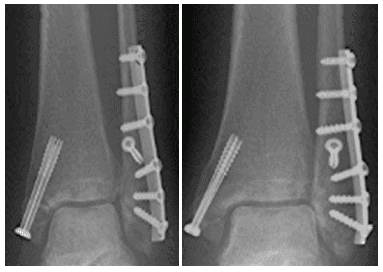

Hầu hết các trường hợp gãy 2 mắt cá chân có thể được nhìn thấy trên hình ảnh X-quang.

Các vết nứt nghiêm trọng nhất cần phải phẫu thuật để làm thẳng xương và đảm bảo khớp mắt cá được đưa trở lại đúng vị trí.